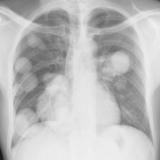

Mets

Album: Mets

Date: 02/18/2006

Size: 52 items

Views: 39306